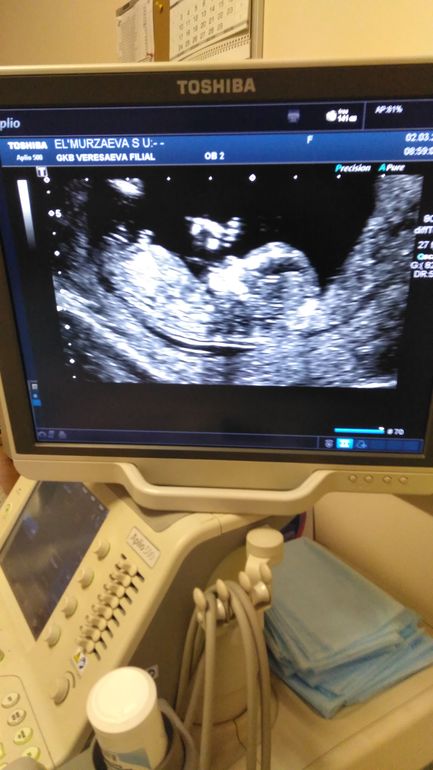

Мама девочки (9 месяцев), жду мальчика, 16 неделя Москва

Мальчик или девочка?

Ну я думаю что это мальчик, потому что что то там торчит

Торчит это пуповина по-моему

Фото неудачное еще, в бесплатной больницу ниче не скажешь ведь

Вроде мальчик, но как то там все размыто 🙈

Помоему мальчик.

Спасибо 😍😍ровно 16 нед, все было предельно видно 😁

По-моему мальчик если по углу наклона смотреть.